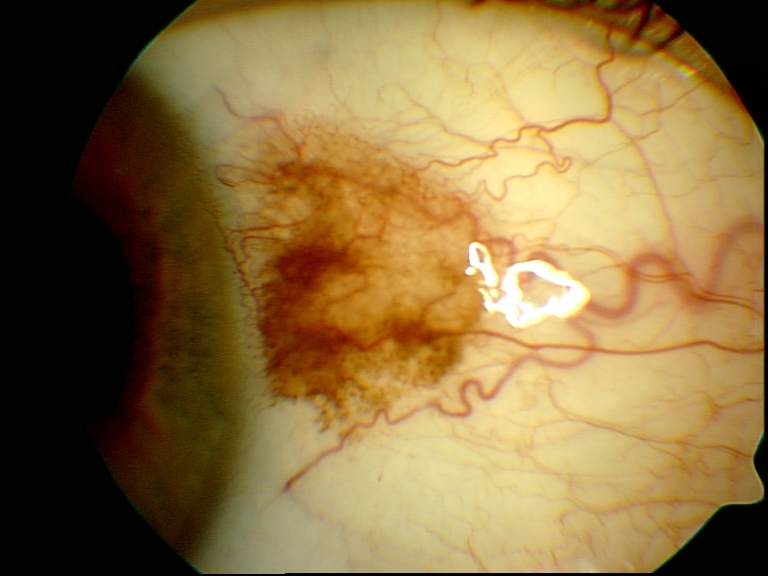

Bild einer Fluoreszenzangiographie